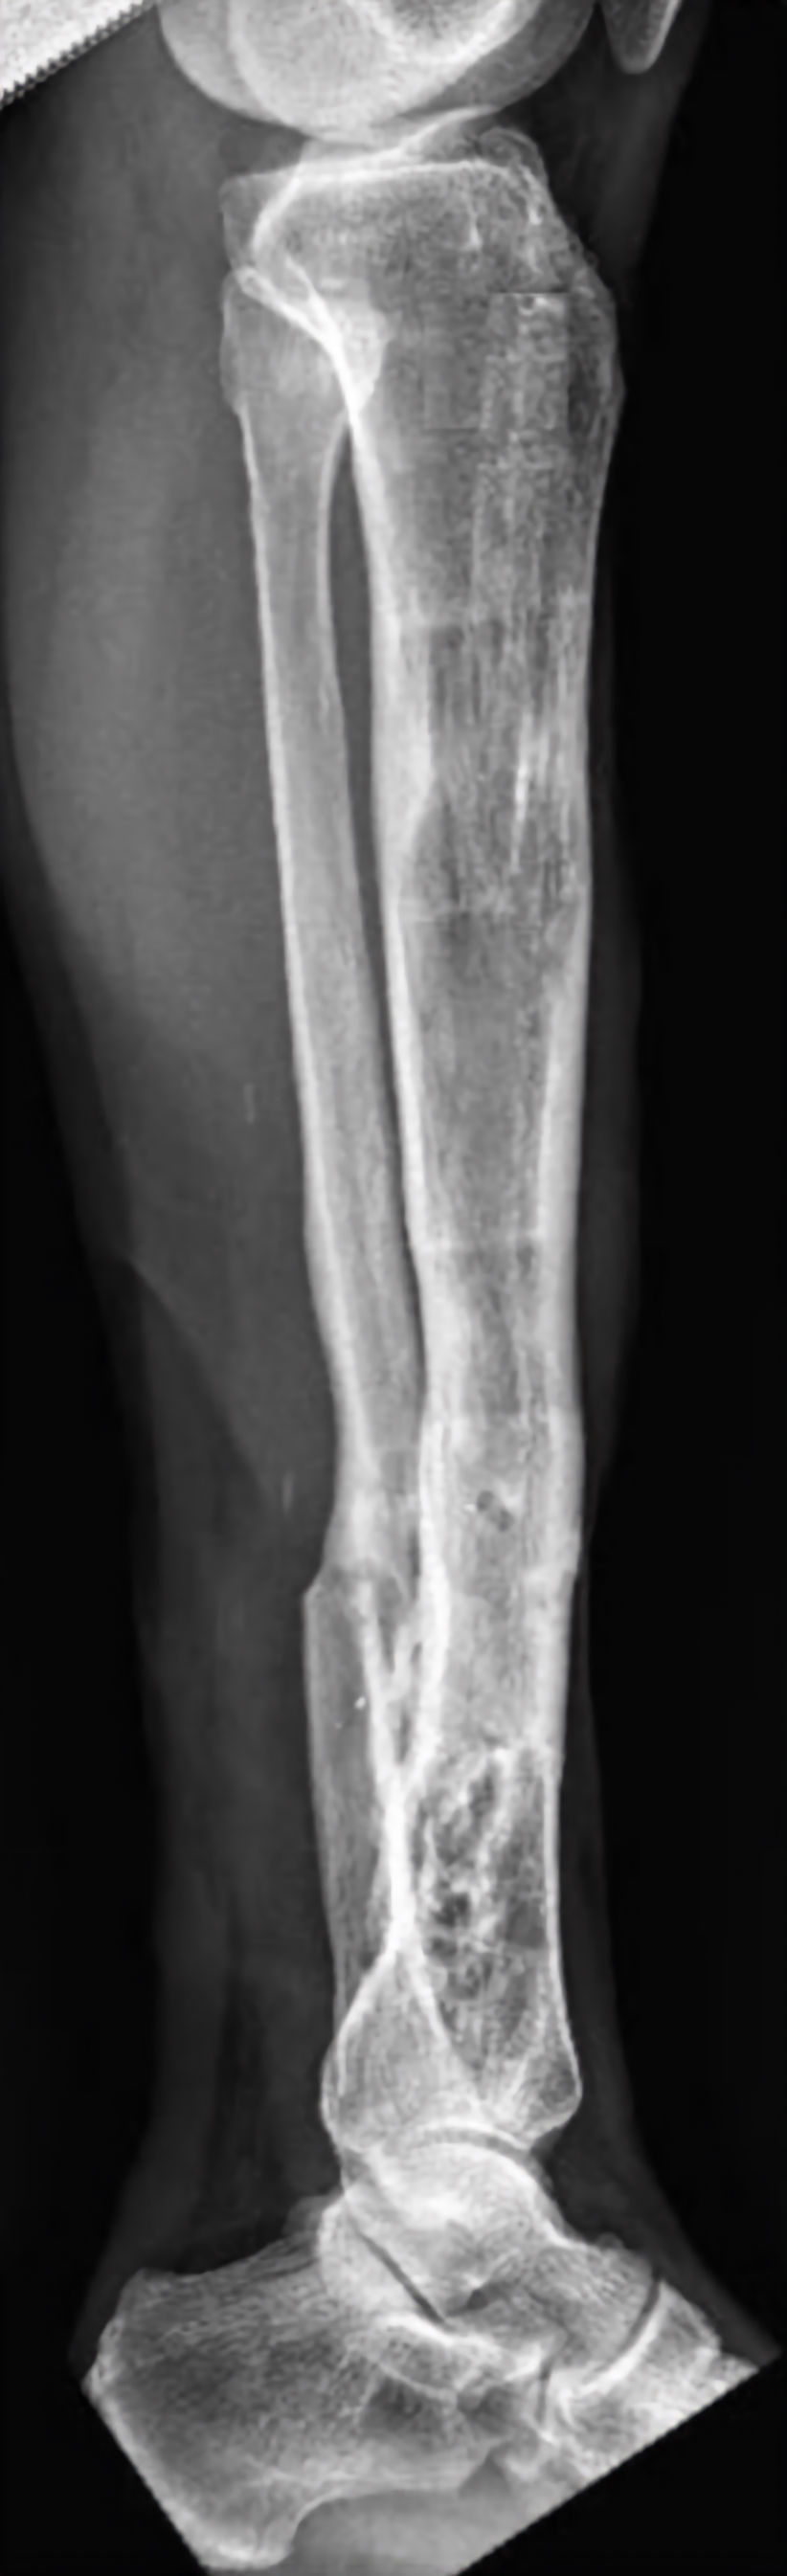

As displasias ósseas são alterações no crescimento e na estrutura dos ossos que podem causar deformidades, encurtamento dos membros superiores e inferiores e causam limitações de função e estética. Em casos mais graves, o osso cresce torto ou enfraquecido, exigindo tratamento especializado.  O método de reconstrução óssea é a principal opção nesses casos. Ele utiliza fixadores externos, como o Ilizarov ou o TL-Hex, ou implantes internos que permitem corrigir deformidades e alongar o osso de forma gradual e segura. Após um corte controlado (corticotomia), o osso é separado milímetro a milímetro, e o corpo forma novo tecido ósseo entre as partes, recuperando o alinhamento e o comprimento natural. Um exemplo é a displasia fibrocartilaginosa focal, em que parte do osso é substituída por tecido fibrocartilaginoso, causando encurvamento progressivo e encurtamento. O tratamento com reconstrução óssea permite realinhar o membro, restaurar o comprimento e melhorar a função. O objetivo final é reestabelecer a forma, o equilíbrio, o movimento, devolvendo ao paciente melhor qualidade de vida.

Já foram catalogadas 771 diferentes entidades associadas a 552 genes. Displasias esqueléticas genéticas representam um espectro amplo e crescente de condições que afetam principalmente a cartilagem de crescimento, o osso, os ligamentos e as articulações — conforme a 11ª revisão da Nosology of Genetic Skeletal Disorders: 2023 Revision. Embora a maioria dos casos envolva mutações em genes que regulam o crescimento endocondral, a morfogénese óssea e a matriz extracelular (por exemplo mutações no gene FGFR3 ou COL2A1, responsáveis por displasias clás­sicas de encurtamento ósseo), há também uma subpopulação relevante de insuficiências de crescimento causadas por fatores endócrinos — como déficit de hormônio do crescimento, resistência ao GH/IGF-1 ou disfunções tiroideias — e de doenças sistêmicas (como doenças metabólicas ou de depósito) que secundariamente interferem no desenvolvimento esquelético. Compreender a etiologia genética, endócrina ou de outro mecanismo (ex: armazenamento lisossomal, excesso hormonal, metabolismo ósseo alterado) torna-se fundamental para o ortopedista, endocrinologista e cirurgião reconstrutor, uma vez que o tratamento, o prognóstico e o acompanhamento diferem vastamente conforme o mecanismo subjacente — e o simples termo “nanismo” ou “encurtamento de membros” pode englobar condições radiologicamente, geneticamente e funcionalmente muito distintas.